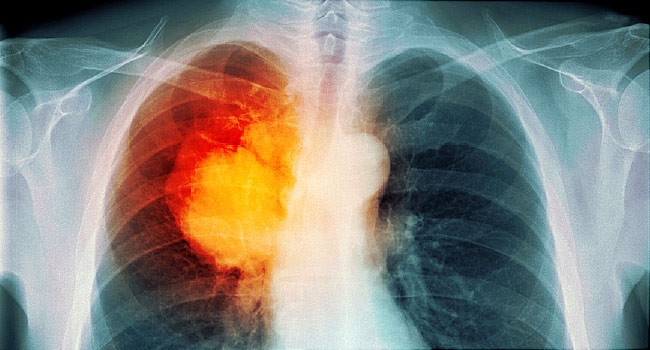

Firstly, X-ray will be advised and if nothing is seen, secondly Ultrasound, CT, MRI, Bone Scan and PET scan will be advised. Lung biopsy, bronchoscopy, mediastinoscopy, thoracoscopy, thoracentesis, video-assisted thoracic surgery, sputum test, molecular tissue test, and pulmonary function test along with arterial blood tests are advised to confirm lung cancer and its stage.